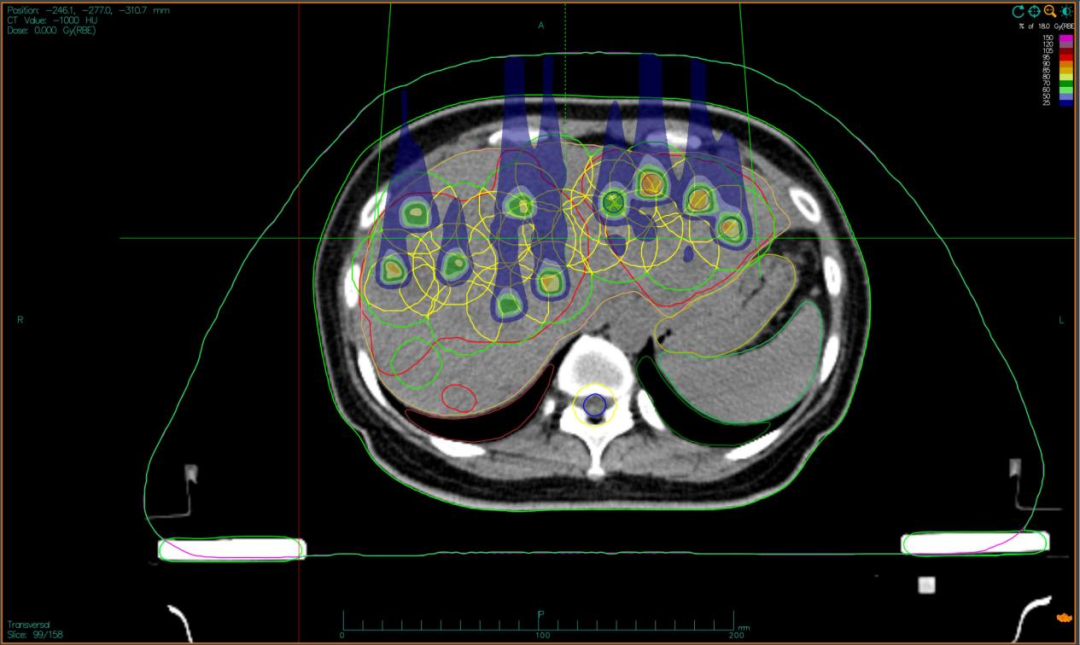

“双布拉格”,并非指代两个物理峰值,而是两大核心治疗理念的深度碰撞与融合。第一个“布拉格”,是物理学范畴的布拉格峰——重离子束流可在体内特定深度释放绝大部分能量,这一特性构筑起“指哪打哪”、极致保护正常组织的物理基石。第二个“布拉格”,是免疫学范畴的布拉格治疗,即国际前沿的PRaG协同治疗方案。它通过精准放疗在局部“点火”,释放肿瘤抗原;以GM-CSF为“导航”,引导免疫系统识别肿瘤细胞;再借助PD-1抑制剂“解除免疫刹车”,让免疫细胞能够持久、全身性地攻击肿瘤,最终追求珍贵的“远隔效应”。而晶格放疗,正是连接两大“布拉格”理念的关键桥梁。针对常规手段无法照射的巨大肿瘤,它将均匀剂量场转化为无数离散的高剂量“能量岛屿”。这种模式不仅能奇迹般保护穿插其中的正常组织与脉管结构,其独特的剂量分布,更被证实可高效诱发免疫原性细胞死亡,将物理打击的能量,转化为激活全身免疫反应的“信号”,让肿瘤的局部治疗与全身控制成为现实。

四大优势协同发力:一,依托重离子射线特有的“布拉格峰”物理特性,实现对深部肿瘤的“定点爆破”;二,采用“晶格放疗”先进布野技术,在巨大肝肿瘤内部精准布设能量“棋盘格”,在高效杀伤肿瘤细胞的同时,为残存正常肝组织与关键脉管留存生存空间;三,将此次精准物理打击,完美嵌入“布拉格治疗”免疫协同策略,以此作为激活全身免疫反应的“点火器”,联合PD-1抑制剂与GM-CSF,力求激发远隔效应,对未被照射的病灶形成攻击;四,引入干细胞支持下的新一代免疫细胞疗法,整合诱导多能干细胞(iPSCs)或间充质干细胞(MSCs)来源的免疫效应细胞(如CAR-T、CAR-NK和TCR-T细胞)与工程化技术,提升癌症免疫治疗的可及性与疗效。